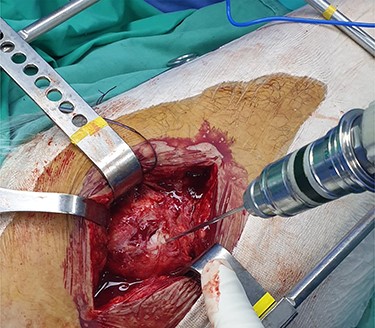

The patient is placed in lateral decubitus position. There is no need of a traction table and fluoroscopy in order to identify the intramedullary canal and the nail inserted. Palpating the prominence of the greater trochanter on the lateral side, an incision is made over it and can be extended distally and proximally. The fasciae latae is carefully incised. The femoral diaphysis and the origin of vastus lateralis are identified. Above the origin of vastus lateralis, k-wires are drilled in order to identify, the anterior and posterior margins of the intramedullary nail in the sagittal plane and mark them and can be left in place (Figs 1 and 2). This is easily performed due to the metal-on-metal effect that is produced during drilling (Fig. 3). Knowing the anterior (point A) and posterior (point P) margins of the intramedullary nail, multiple drillings are performed proximally and perpendicular to the median of the (AP) side of the formed triangle (TAP). The drilling point where no metal-on-metal effect is produced corresponds to the proximal endpoint of the intramedullary nail (point T). Those points form a triangle (TAP) on the lateral side of the femur with the top (T) highlighting the endpoint of the intramedullary nail, and the sides the anterior (A) and posterior (P) margins (Fig. 4). Drilling with k-wires also helps us determine the depth of the nail.

Intraoperative image showing the position of a k-wire in order to indentify the posterior margin of the intramedullary nail.